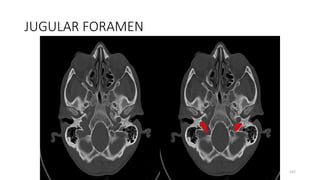

Jugular foramen

Content

• Internal jugular vein,

• Inferior petrosal sinus,

• Sigmoid sinus

• Glossopharyngeal nerve (IX),

• Vagus nerve (X),

• Accessory nerve (XI)

45

147